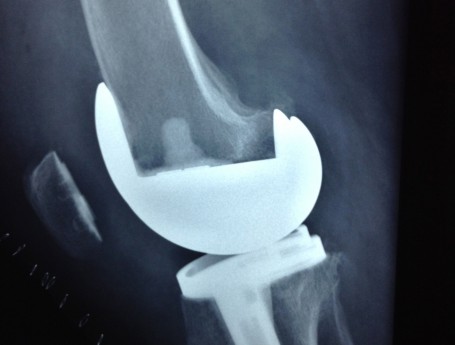

Revision Total Knee Replacement After Infection

• Revision Total Knee Replacement After Infection